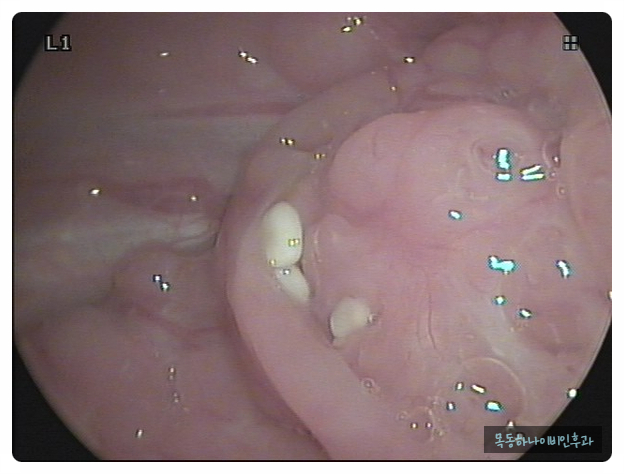

편도결석은 편도선 내에 있는 얇고 깊은 홈에 음식물 찌꺼기나 각종 분비물이 침착되어 돌처럼 굳어진 물질입니다. 크기는 눈곱처럼 작지만 손톱 크기만큼 큰 결석이 나오기도 합니다. 색깔도 다양하기 때문에 흰색에서 노란색이나 치즈색을 보이기도 합니다. 건강한 성인이라도 약 10%에는 편도결석이 관찰됩니다. 물론 편도 결석이 있지만 결석이 있을지도 모른다는 분들도 많습니다.

편도결석은 눈으로 확인하면 바로 진단이 가능합니다. 양치질이나 기침을 할 때 튀어나오거나 눈에 보이는 경우도 있습니다. 증상은 있지만 눈으로 관찰되지 않을 때 병원에서 후두 내시경으로 목 안쪽에서 관찰될 수도 있습니다.